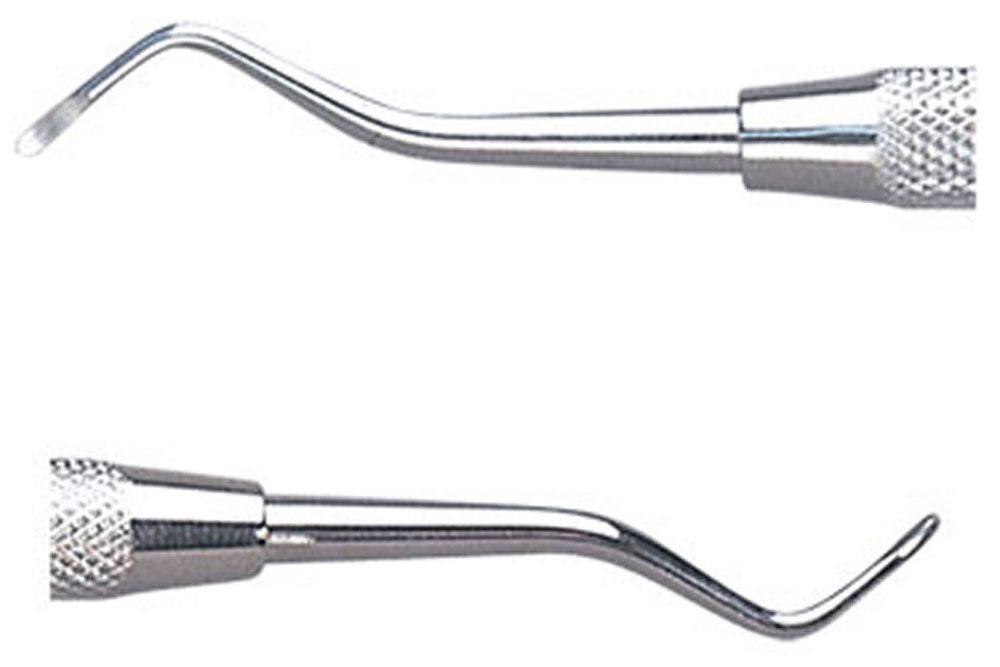

2、「5倍速コントラ」「スプーンエキスカベーター」で削る量を最小限に

虫歯に感染した部分は「軟化象牙質」と呼ばれ、歯が軟らかくなってしまっています。普通ならばこの部分をドリルによって一気に削りますが、ドリルは健康な歯まで削ってしまう可能性があります。 そこで、当院ではドリルだけで済ませることなく、ある程度ドリルで削ったら「スプーンエキスカベータ―」を使い、手の感触によって見極めながら軟化象牙質の除去を行っています。

ただドリルで削るだけよりも少し時間がかかりますが、出来る限り健康な歯を削らずに残すという当院のこだわりと考えていただければ幸いです。